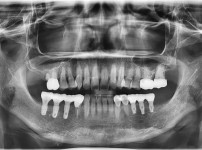

전체임플란트

임플란트